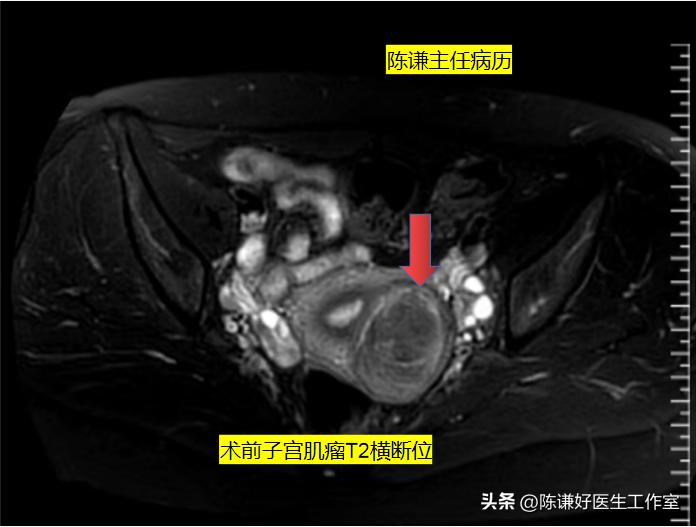

病人术前超声显示肌瘤大小接近6cm,凸向浆膜;患者磁共振显示左侧壁肌瘤,肌瘤位于肌壁间。

术前磁共振图片